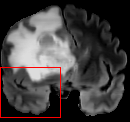

To test the impact of the iterative refinement on YODA’s translation quality, we compared regression and diffusion sampling on the RS data and present additional generation examples in Fig. 6. We observe that diffusion sampling visually resembles the appearance of the acquired images. Regression sampling preserves key anatomical features – the GM/WM boundary, WMHs (Fig. 4), the outline of the pallidum (Fig. 6) – but omits many high-frequency features. To investigate whether iterative refinement during diffusion sampling adds relevant and systematic medical information or only imitates acquisition noise, we performed ExpA sampling, i.e. averaging the output of several ( or ) diffusion trajectories. We observed a gradual loss of high-frequency details when increasing the (see also the supplementary video), indicating that the effect of the iterative refinement is non-systematic. For , the images are visually almost indistinguishable from the initial regression solution (see the supplementary video, and Fig.4 and 6). We directly compared the synthesis results of ExpA () and regression sampling quantitatively and found the differences to be minimal (SSIM: 99.73%, PSNR: 45.30 dB), i.e. diffusion sampling approaches the initial regression solution for a high . The quantitative analysis of the image quality (Tab. 1) showed that diffusion sampling impairs the assessed SSIM and PSNR in comparison to regression sampling for both the in- and external test sets, which we attribute to noise generation (Sec. 3.1). In turn, ExpA averages improved both metrics and, for , performed mostly on par with the regression solution in both test sets in terms of SSIM, while the PSNR in the RS was slightly increased (Tab. 1). However, we observed that ExpA sampling YODA improves the replication of systematic 3D low-frequency image intensity drifts (bias fields) due to the 3D synchronization in 2.5D diffusion sampling. Yet, this apparent advantage did not generalize to the external MBB dataset, as bias fields are MR protocol-specific.

To assess the suitability of YODA-generated images for WMH detection independent of segmentation tools, we also calculated the CNR (15) of WMHs. This confirmed that the contrast of WMHs is preserved in the regression images, whereas we noted slightly reduced WMH contrast for diffusion and ExpA-sampled images (Tab. 1).

We therefore conclude that, beyond slight benefits in fostering 3D coherency, iterative refinement does not have a systematic effect, i.e. the expected value of the diffusion sampling corresponds to the initial regression solution and diffusion sampling does not improve image quality beyond perceptual realism.

However, we observed some missing small WMHs (third row, Fig. 9) in the synthetic FLAIR images. Due to the weak input signal, translating small WMHs in inherently difficult and, thus, omitting these WMHs can be seen as conservative. In contrast, a more speculative translation bears the risk of false-positive, hallucinated WMHs (compare e.g., SynDiff, Fig. 4).